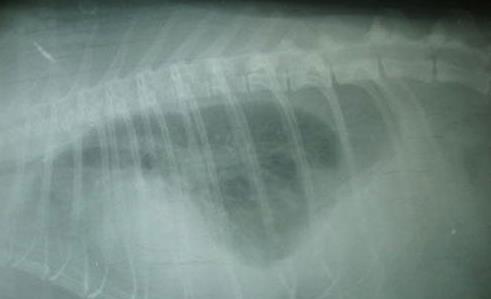

乳糜胸拍片

乳糜胸是指乳糜在胸腔内聚积。乳糜来自胸导管、胸导管内有来自身体的富含脂质的淋巴液。乳糜通常眼观为白色并且浑浊、主要是因为其中的乳糜微粒、偶然乳糜液也会带淡血色,也有可能为澄清和无色液体、特别是在厌食的动物。